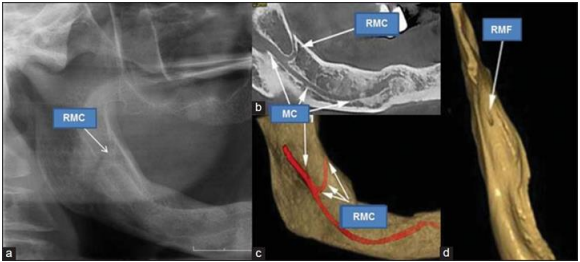

Prevalence, dimension and location of retromolar canal on cone beam computed tomography : An Analytical cross sectional study

Prevalence, dimension and location of retromolar canal on cone beam